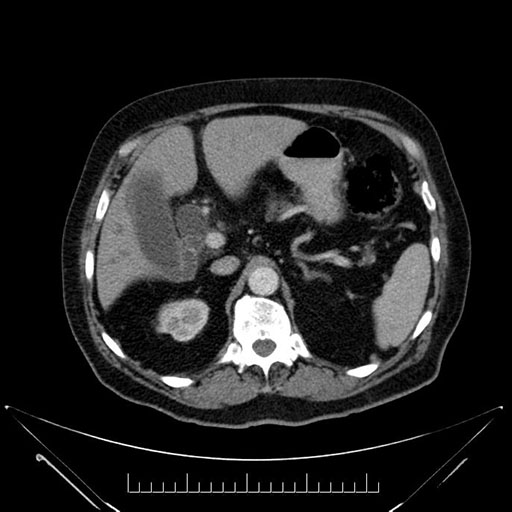

Whipple (pancreaticoduodenectomy) [case 7]

Imaging Analysis

Look through the patient's CT scan to identify any areas of concern for the necessary procedure.

Based on your CT findings, which issue(s) would give reason for "planned slowing down moment(s)" in this case?

Considering a standard Whipple procedure, what step(s) of the operation would you do differently in this case?